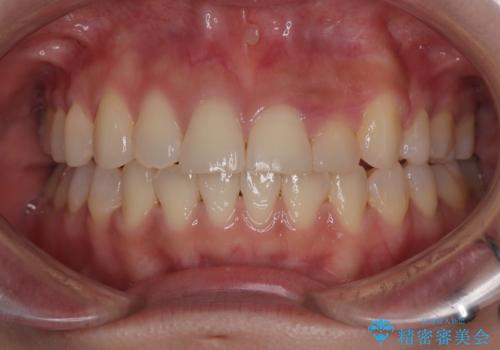

- 左上の前歯のがたつきを主訴に来院された患者様です。

上顎歯列が下顎の歯列に対して狭小であり、一部下顎の奥歯が上顎よりも外側に位置している状態でした。

上顎の歯列を拡大しスペースを設け、さらに左上の小臼歯を一本抜歯し左上の八重歯を歯列内に入れ整えていくことにしました。